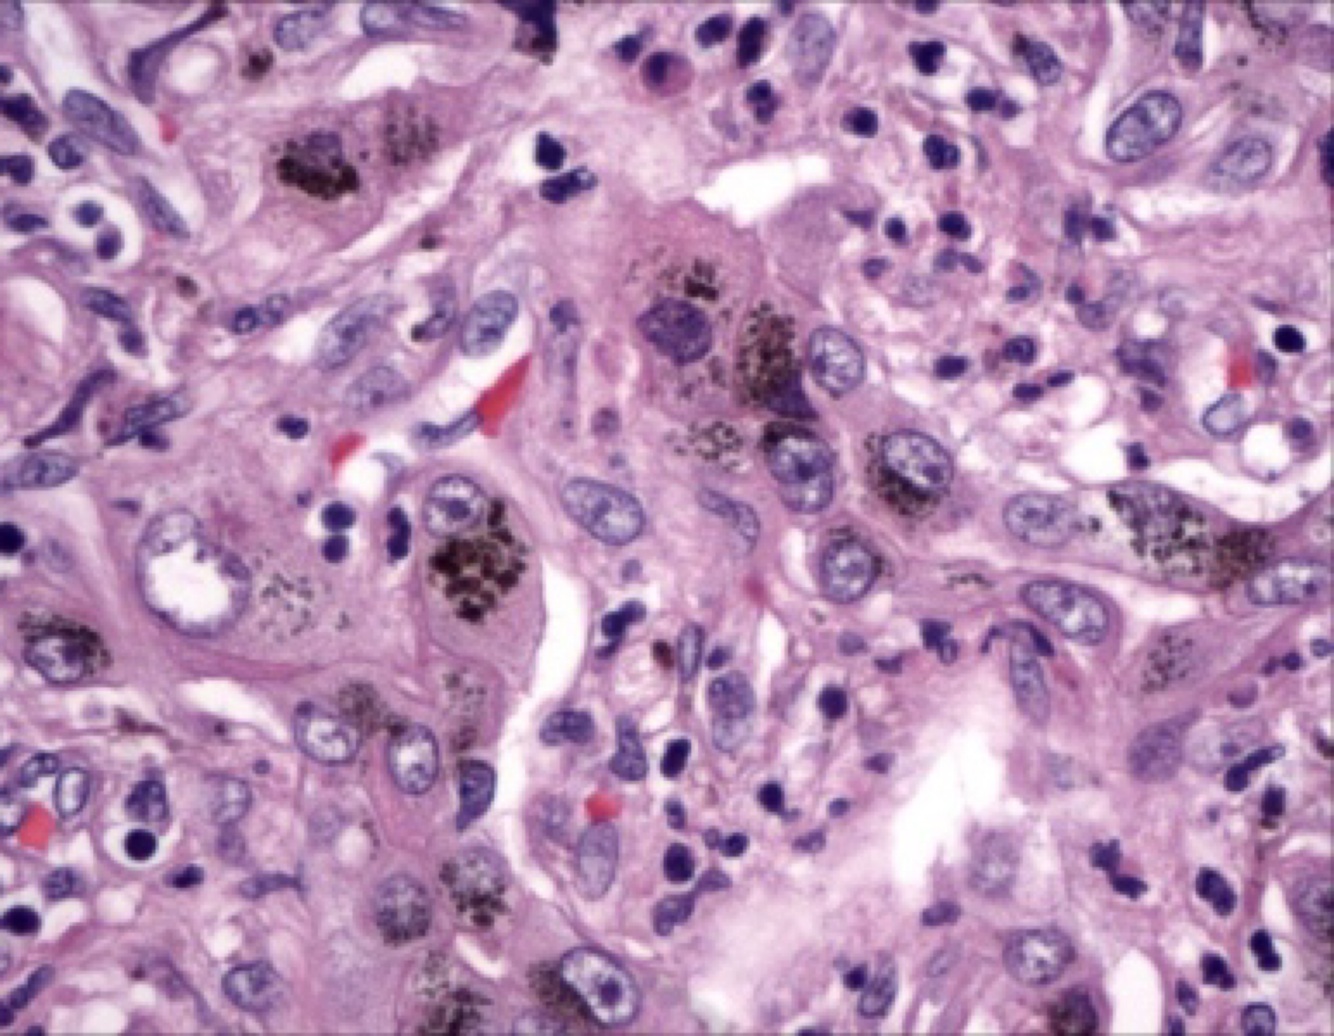

Krukenberg tumors: signet-ring” cells I